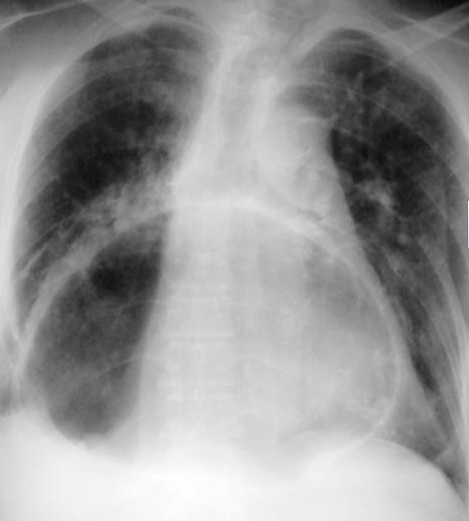

Red arrows – Rectal stromal tumor. Multiple liver metastases (Courtesy Dr. V. Penopoulos)